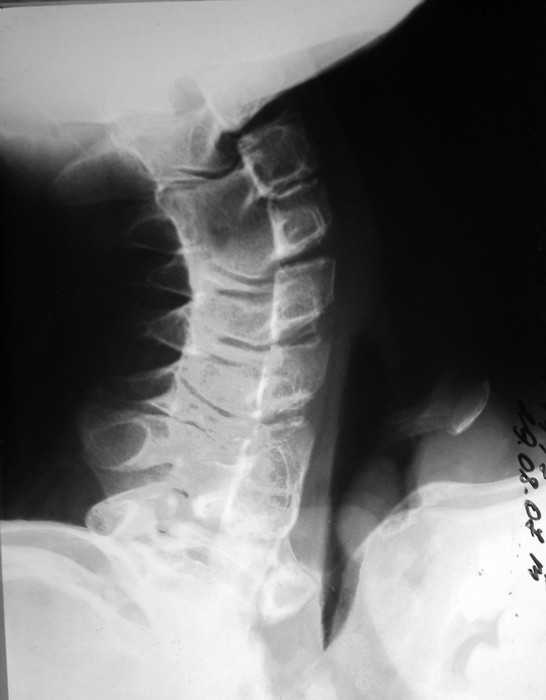

Жалобы: на нарушение функции верхних конечностей: невозможность движения в обеих правых плечевых и локтевых суставах; ограничение движений в шейном отделе позвоночника, наличие опухолевидных множественных образований на спине и пробам бедре.

Анамнез заболевания: со слов матери появлению множественных опухолевидных образований на спине предшествовал массаж воротниковой зоны в 4 года. Консультирован в Областной детской больнице и Областном онкодиспансере. В декабре 2010 г. после падения с велосипеда ушиб левый локтевой сустав, a в январе вторичное падение с велосипеда с ушибом правого локтевого сустава, после чего пациент отметил постепенное ухудшение функции обеих верхних конечностей вплоть до резкого ограничения объема движений в обеих плечевых и локтевых суставах.

Место болезни: при осмотре определяется - вынужденное положение верхних конечностей в плечевых и локтевых суставах, множественные опухолеподобные образования вдоль позвоночника и по наружной поверхности верхней трети левой бедренной кости округлой формы, с четкими контурами, неподвижные, безболезненные, каменистой плотности. приводяще-отводящая контрактура в обеих плечевых суставах, сгибательно-разгибательная контрактура в обеих локтевых суставах с сохранение про- и супинационных движений. Объем движений в пальцах кисти и лучезапястных суставах в полном объеме без ограничений, безболезненный.

Диагноз: врожденная аномалия развития шейного отдела позвоночника с резким нарушением функции в плечевых и локтевых суставах, множественных костно-хрящевые экзостозы, оссифицирующий миозит.

рентгенограммы

это fibrodysplasia ossificans progressiva, генетически обусловленная прогрессирующая метаплазия соединительной и мышечной ткани в костную. Лечится (вернее, тормозится) консервативно, после попыток оперативного лечения и после травм - прогрессирует.